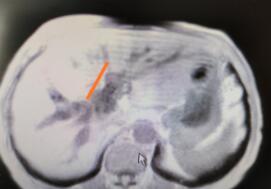

患者是一位71岁的老人,半个月前出现皮肤瘙痒,全身皮肤黄染,从当地一家医院转诊湘雅二医院肝脏外科。接诊后,戴卫东教授团队为患者进行检查后,确诊为Bismurth IV型肝门胆管癌。

与传统手术相比,机器人手术仅需4个1厘米的小切口,所有的手术操作均依靠机械手完成。随着戴卫东教授的操纵,机器手臂灵巧、精准地实施操作,完整切除肝门部肿瘤,残余胆管远端均达到R0切除(无癌残留)。“高度放大的3D手术视野几乎无任何死角,可以更加清晰地暴露肝门淋巴及神经结缔,便于肝门部淋巴及神经结缔组织彻底清扫。完整切除肝门部肿瘤后,再行左肝管空肠内引流及右肝管、尾叶胆管围肝门空肠吻合,吻合方便、严密,极大地减少了术后胆漏的发生率,同时,最大程度上避免了对正常肠管的损伤。”戴卫东介绍,手术历时4小时,术中出血仅100ml,术后第2天患者开始进食,黄疸逐步下降,并于术后第5天顺利出院。